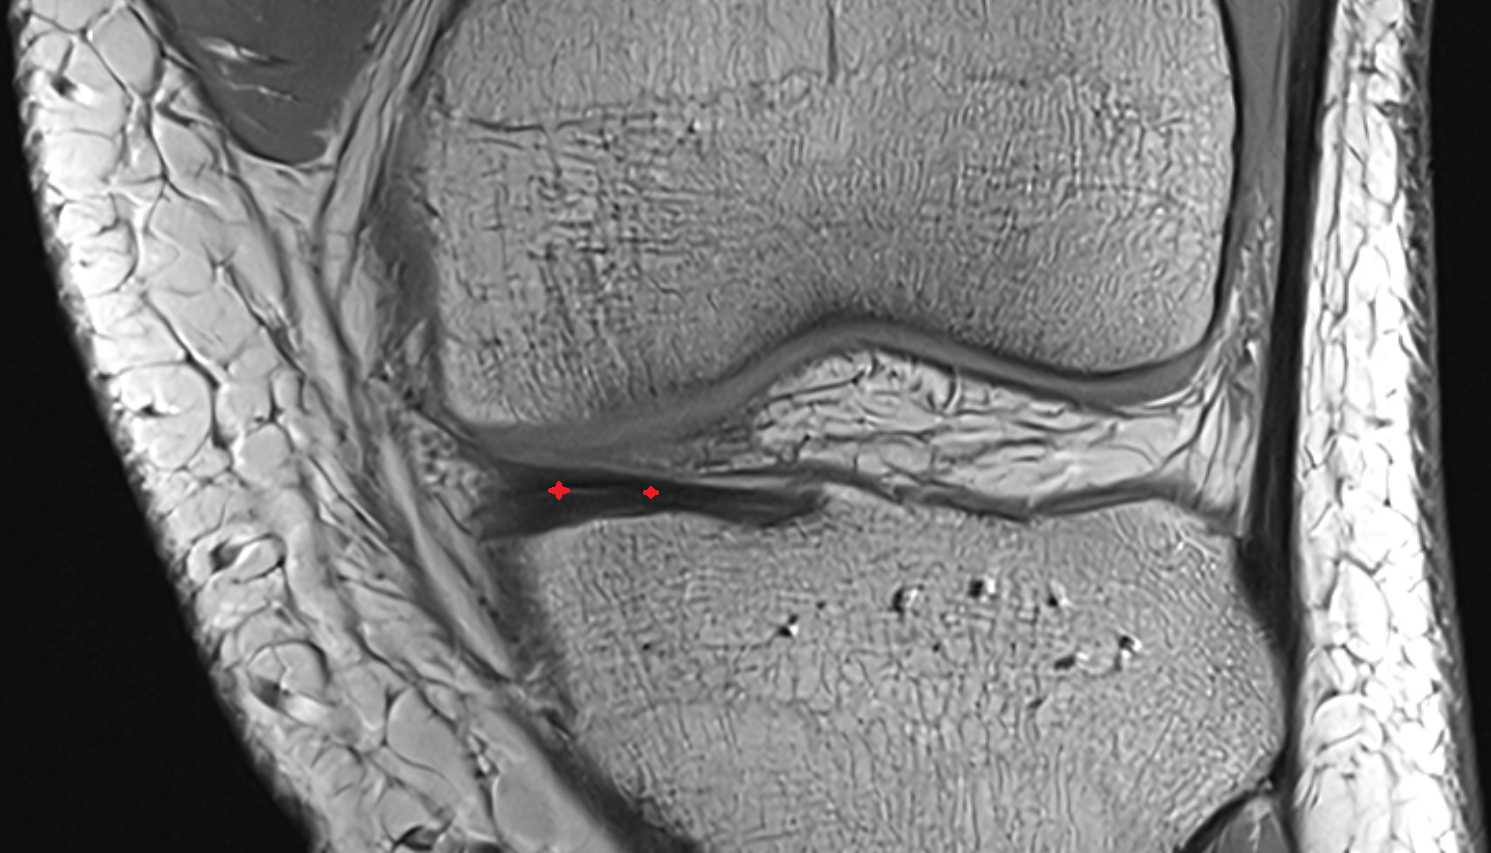

- Medial collateral ligament

- Medial meniscus

- Anterior horn of medial meniscus

- Posterior horn of medial meniscus

- Body of medial meniscus

- Anterior root of medial meniscus

- Posterior root of medial meniscus